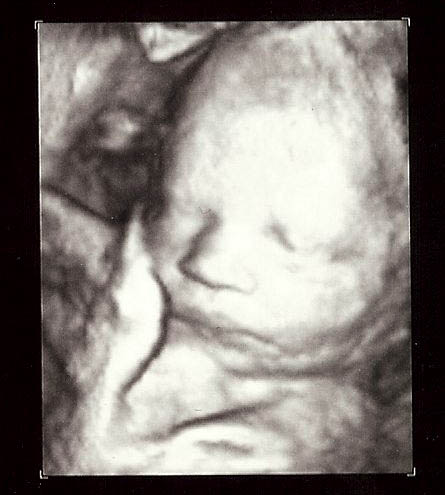

Okay, the doctor has decided the little guy in the photo below will be introduced to the hard, cold reality of this world on Thursday, April 7, 2011.

At this time, both mother and baby are fine. However, mother wouldn’t be disappointed if today were April 6. Please pray for her as she waits another nine days.